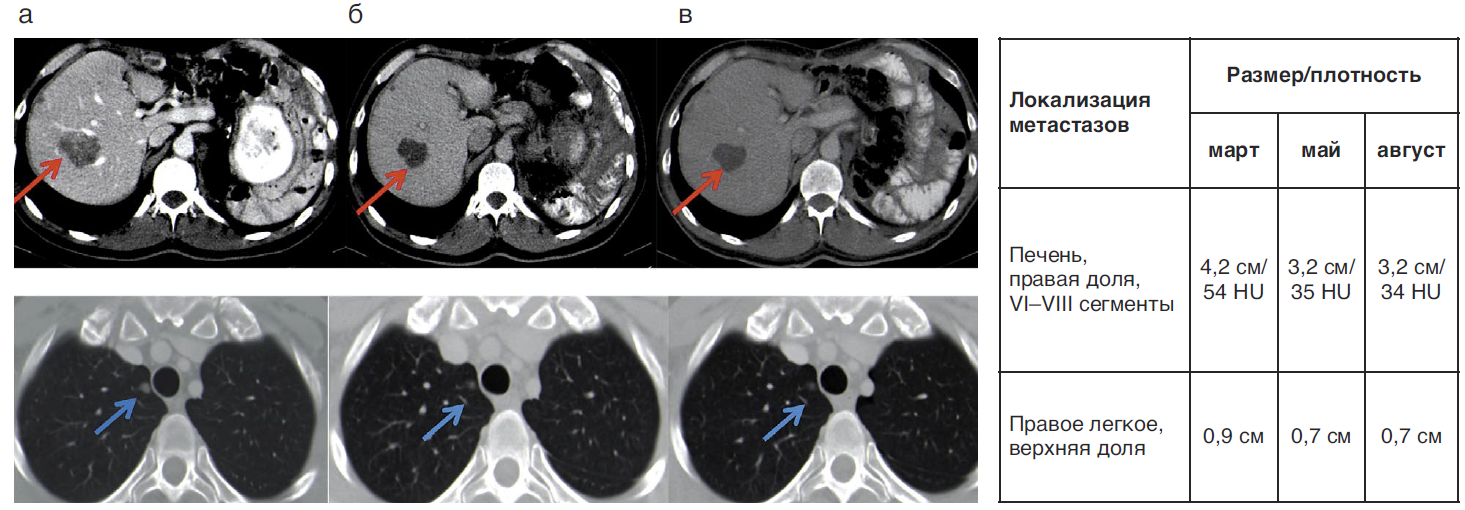

С марта 2019 г. пациент начал терапию авапритинибом 300 мг/сут в 6-й линии. Через 3 мес терапии размеры и плотность контрольных метастазов в печени уменьшились и уменьшились размеры метастазов в легких – достигнута частичная регрессия (рис. 3).

Рис. 3. Компьютерная томография в динамике (а – март 2019 г., б – май 2019 г., в – август 2019 г.), контрольный метастаз в правой доле печени в VI–VIII сегментах, контрольный метастаз в в верхней доле правого легкого.

Fig. 3. Dynamic computer tomography (a – March 2019, b – May 2019, c – August 2019), to control metastasis in the right lobe in segments VI–VIII of the liver, to control metastasis in the upper lobe of the right lung.

Эффект сохранялся до декабря 2019 г. (9 мес). Самыми ранними побочными эффектами были периорбитальные отеки и повышенное слезотечение. Через 3 мес отмечена гематологическая токсичность, что потребовало коррекции дозы до 200 мг/сут. В сентябре 2019 г. отмечены когнитивные нарушения – кратковременное нарушение памяти. Лечение пациента О. суммировано в табл. 5.